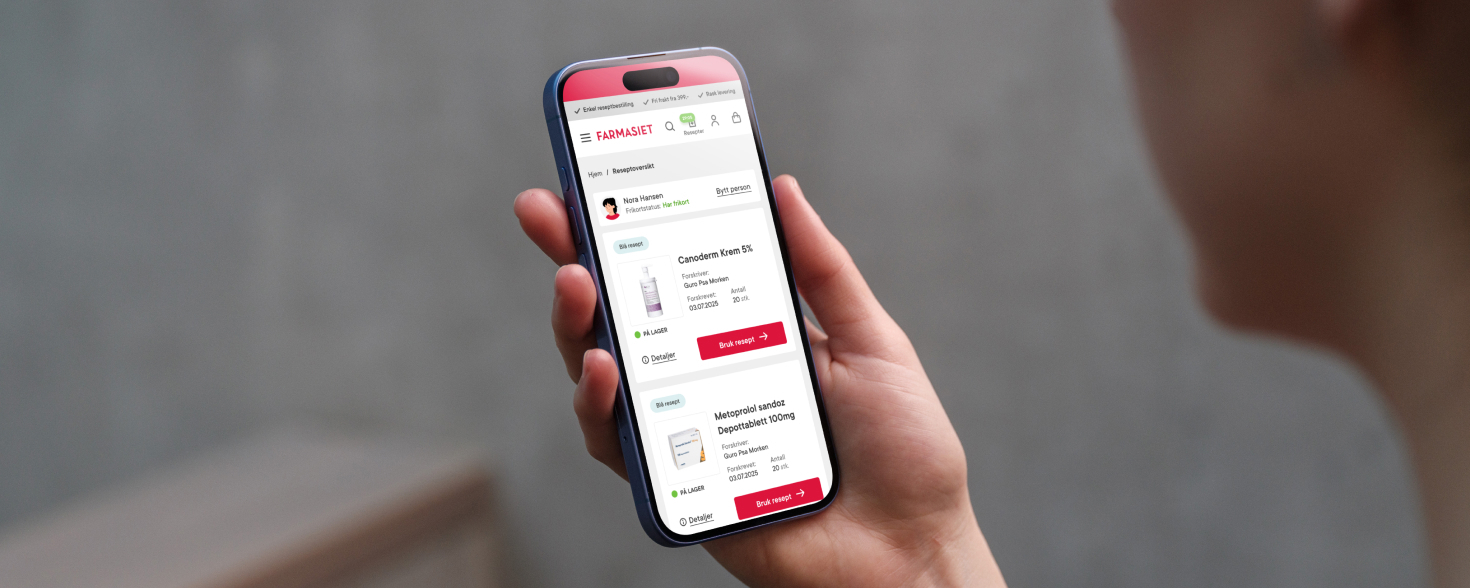

Hent resepter for deg selv eller barnet ditt

- Logg inn med BankID eller annen eID og få sikker tilgang til alle dine resepter

- Velg hvilke resepter du vil hente ut og hvordan du vil ha dem levert

- Få dine resepter levert raskt og trygt på avtalt måte